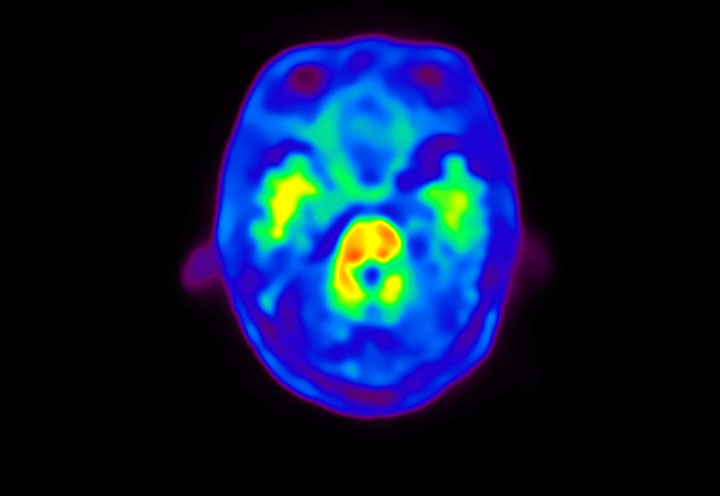

Head / Case4 : Amyloid

Sagittal

Courtesy : Kindai University Hospital

- Imaging protocol

- Injected dose: 3.21 MBq/kg, 18F-Flutemetamol

- Uptake time: 100 minutes

- Scan time: 20 minutes